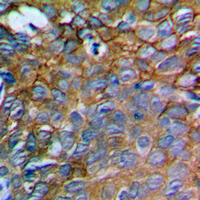

IHC (Immunohiostchemistry)

(Immunohistochemical analysis of IL-12A staining in human prostate cancer formalin fixed paraffin embedded tissue section. The section was pre-treated using heat mediated antigen retrieval with sodium citrate buffer (pH 6.0). The section was then incubated with the antibody at room temperature and detected using an HRP conjugated compact polymer system. DAB was used as the chromogen. The section was then counterstained with haematoxylin and mounted with DPX.)